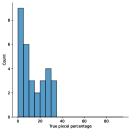

A few sample images and the corresponding masks of the polyp dataset in HyperKvasir are shown in Fig 2. The polyp images are RGB images. The masks of the polyp images are single-channel images with white () for true pixels, which represent polyp regions, and black () for false pixels, which represent clean colon or background regions. In this dataset, there are different sizes of polyps. The distribution of polyp sizes as a percentage of the full image size is presented in the histogram plot in Fig 3, and we can observe that there are more relatively small polyps compared to larger polyps. Additionally, a subset of this dataset was used to prove that the performance of segmentation models trained with small datasets can be improved using our SinGAN-Seg pipeline, and the whole dataset was used to show the effect of using SinGAN-Seg generated synthetic images instead of a large dataset which has enough data to train segmentation models. In this regard, this dataset was used for two purposes:

To understand the difference between the mask distribution of real images and synthetic images, we plotted pixel distribution of masks of synthetic images in Fig 6. This plot is comparable to the pixel distribution presented in Fig 3. The randomness of the generations made differences in the distribution of true pixel percentages compared to the true pixel distribution of real masks of real images. However, the overall shape of synthetic data mask distribution shows a more or less similar distribution pattern to the real true pixel percentage distribution.